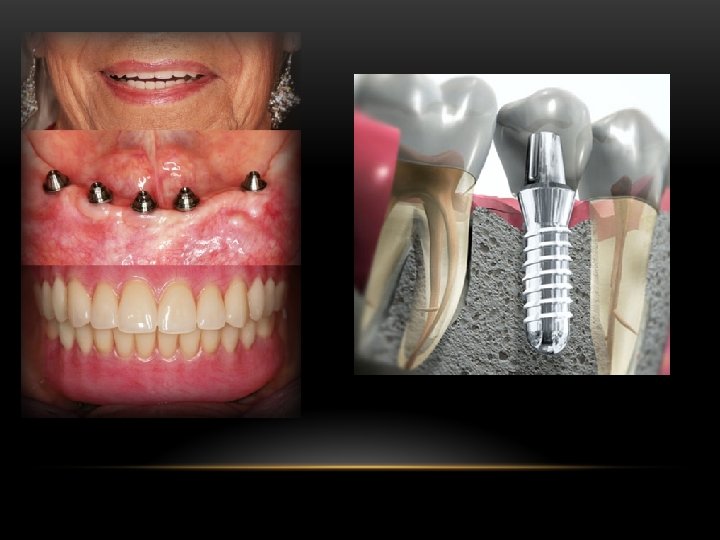

Implantología La implantología dental es la disciplina de la odontología que se ocupa del estudio de los materiales aloplásticos dentro o sobre los huesos de maxilares para dar apoyo a una rehabilitación dental. Tiene como objetivo sustituir dientes perdidos mediante la colocación quirúrgica de un implante dental en el hueso maxilar o mandibular